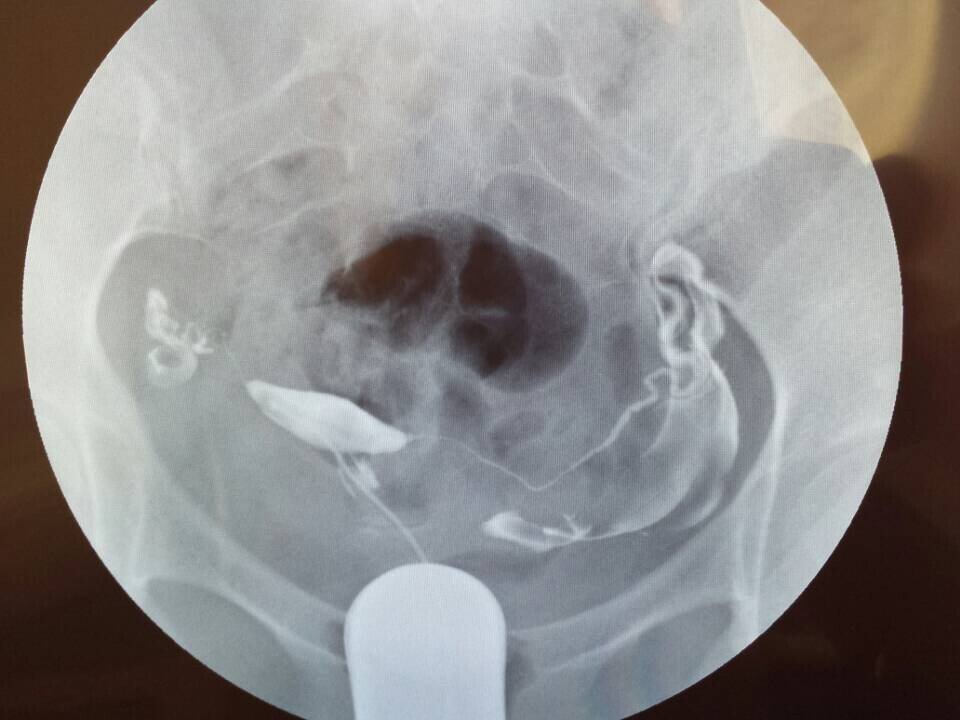

求医生帮我看一下输卵管造影的片子,在当地的妇婴医院造影后,医生太忙,没有给仔细讲解,希望专家帮我看下该采用什么方案,是否严重,如何治疗,跪谢!~有慢性阑尾炎病史,月经周期一直不准,40-50天左右来一次月经,雌激素比较低,一直在喝中药调理月经。备孕6个月监测排卵但是一直没有怀孕,这个月初做了碘油输卵管造影,当时患者太多,大夫没有做过多讲解,就给开了两盒治疗盆腔炎的药,也没有告诉用不用挂吊瓶消炎,现在造影后一个星期了,右侧输卵管部位每天都会隐隐的疼,是否该需要输液呢?